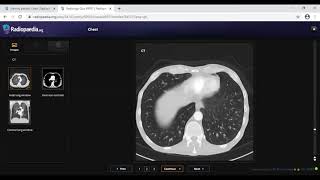

Radiology Viva Practice Case: 2 - FRCR 2B preparation